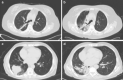

Chemo-radiotherapy and systemic therapies have proven satisfactory outcomes as standard treatments for various thoracic malignancies; however, adverse pulmonary effects, like pneumonitis, can be life-threatening. Pneumonitis is caused by direct cytotoxic effect, oxidative stress, and immune-mediated injury. Radiotherapy Induced Lung Injury (RILI) encompasses two phases: an early phase known as Radiation Pneumonitis (RP), characterized by acute lung tissue inflammation as a result of exposure to radiation; and a late phase called Radiation Fibrosis (RF), a clinical syndrome that results from chronic pulmonary tissue damage. Currently, diagnoses are made by exclusion using clinical assessment and radiological findings. Pulmonary function tests have constituted a significant step in evaluating lung function status during radiotherapy and useful predictive tools to avoid complications or limit toxicity. Systemic corticosteroids are widely used to treat pneumonitis complications, but its use must be standardized, and consider in the prophylaxis setting given the fatal outcome of this adverse event. This review aims to discuss the clinicopathological features of pneumonitis and provide practical clinical recommendations for prevention, diagnosis, and management.